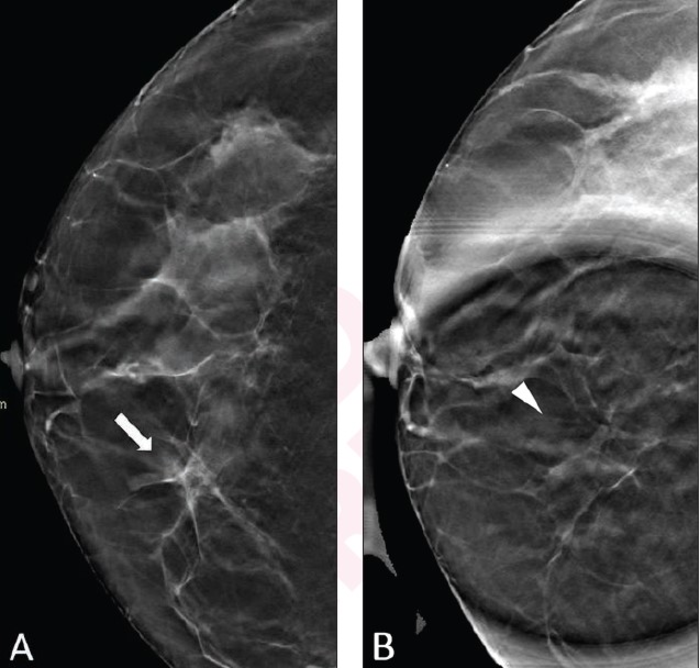

Leesburg, VA, February 16, 2022 According to an article in ARRS’ American Journal of Roentgenology ( AJR ) , digital breast tomosynthesis (DBT) spot compression view could help characterize equivocal DBT findings, thus reducing further workup for benign findings.

Noting that DBT spot compression increased both intrareader and interreader agreement and improved diagnostic accuracy, primarily from improved specificity, “the view’s supplemental dose was slightly higher than that of a standard DBT view,” corresponding author Foucauld Chamming’s of Institut Bergonié in Bordeaux, France acknowledged.

The all-French team’s retrospective study included 102 women (mean age, 60 years) for whom a DBT spot compression was acquired to characterize an equivocal finding on DBT (via the performing radiologist’s discretion) from December 14, 2018 to December 18, 2019. Conscious of the equivocal lesions’ location, two fellowship-trained breast radiologists and one breast imaging fellow independently reviewed all examinations—assigning an initial BI-RADS category using standard DBT views, immediately followed by a category using DBT spot compression.

Based on kappa coefficients for DBT with and without spot compression views, intrareader agreement increased from 0.43 to 0.72, and interreader agreement increased from 0.21 to 0.45. Additionally, for all three readers, DBT spot compression views yielded significantly increased accuracy, as well as significantly increased specificity.

Adding that their study is the first to evaluate the impact of obtaining DBT spot compression for equivocal findings on DBT, “the results support the utility of spot compression views for aiding evaluation of subtle or ambiguous findings encountered on DBT in clinical practice,” the authors of this AJR article concluded .